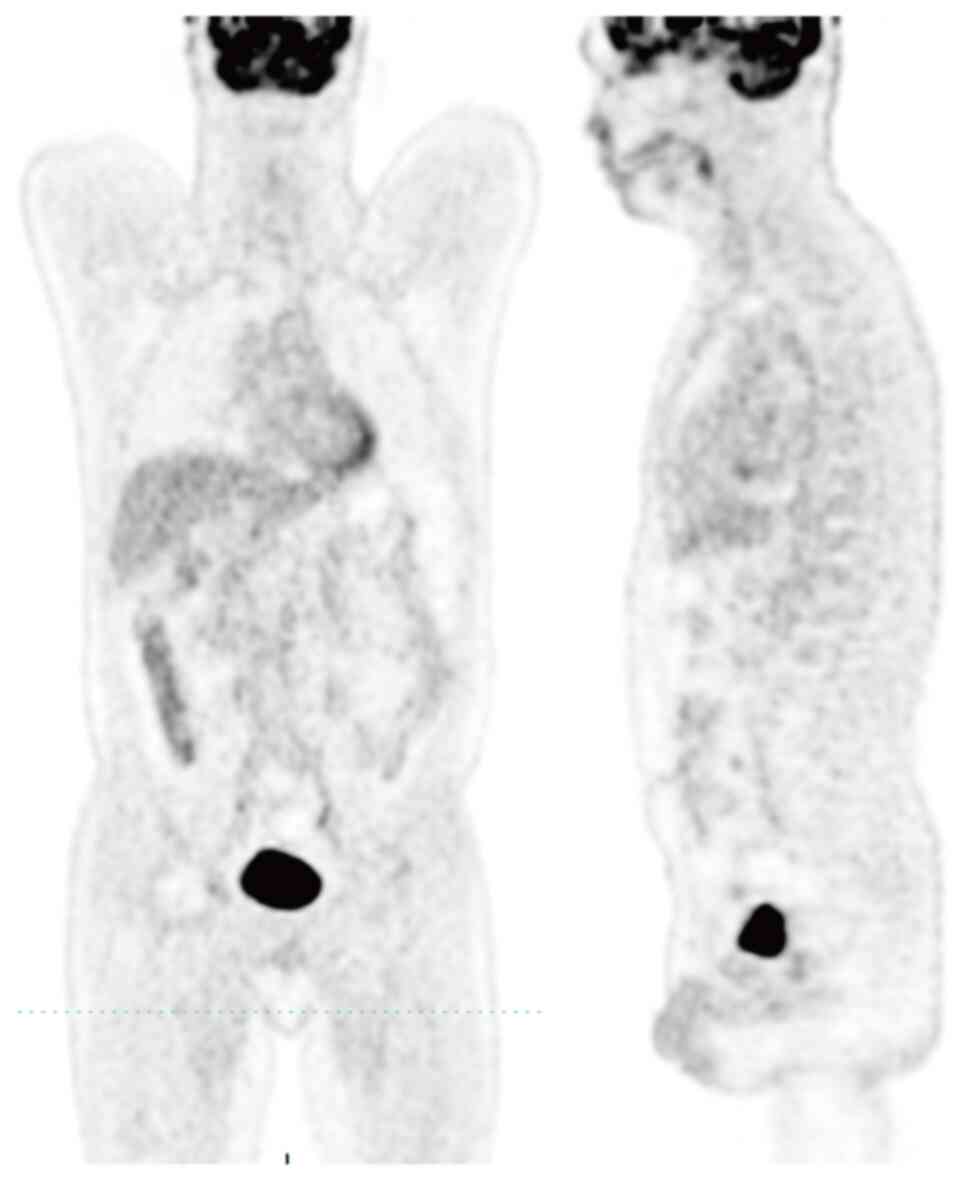

Primary gingival diffuse large B‑cell lymphoma (DLBCL) with muscle invasion is rare and accounts for ~0.5% of all reported cases of extranodal lymphoma. The present study describes the case of a 49‑year‑old man that initially presented at Yingshan County People's Hospital (Nanchong, China) in August 2017 with a chief complaint of tenderness and swelling of the jaw. Computed tomography revealed a mass in the gingiva, and enlarged lymph nodes in the cervical, mediastinal and gastro‑hepatic ligaments. Histological examination indicated the gingival mass was a DLBCL, which was positive for CD20, BCL‑6, BCL‑2, C‑MYC and MUM1. The patient received three lines of anti‑neoplastic therapy (R‑CHOP, R‑CHOEP and SYHX1903) and achieved stable disease for 6 years. Subsequently, the patient experienced trauma in the left forearm due to a car accident and the subsequent color Doppler imaging led to a diagnosis of muscular hematoma; however, magnetic resonance imaging and biopsy of the forearm muscle confirmed DLBCL invasion. Due to the patient suffering from heart failure after the third line of the previous chemotherapy, palliative radiotherapy was administered to the left forearm, and the patient achieved a partial response. In conclusion, primary gingival DLBCL with muscle invasion is rare and easily misdiagnosed, and individualized treatment should be considered for these complex cases.

Figure 2